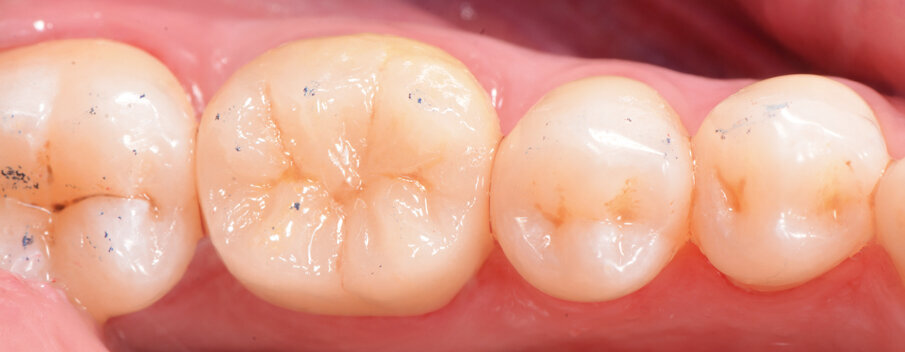

Fig. 2: Situation after composite build-up (Tetric N-Ceram Bulk Fill) and preparation.

A 45-year-old male patient presented to the practice with a restoration on tooth #46. The tooth had been endodontically treated and temporised with a filling (Fig. 1). The temporary was removed, the tooth built up with Tetric N-Ceram Bulk Fill (Ivoclar Vivadent) and then prepared for the crown restoration (Fig. 2). An impression was taken with a one- step, two-phase impression technique using a putty and light-body silicone. After scanning the model, the crown was designed in the software suite (inLab, Dentsply Sirona) and milled from an IPS e.max CAD lithium disilicate block (Ivoclar Vivadent; Figs.3a & b). After the crystallisation fir- ing, the crown was stained and glazed (Fig. 4). The next step was to etch and silanate the ceramic crown with the new glass-ceramic primer Monobond Etch & Prime (Ivoclar Vivadent). This primer combines a ceramic etching and silanating component in a single material and therefore eliminates the need for the ceramic to undergo hydrofluoric acid etching (Fig. 5). After the etching and silanating step, the crown was rinsed with water and dried. The isolated enamel was then etched (Fig. 6). The adhesive (Tetric N-Bond Universal) was applied and dispersed with a strong stream of air. The dual-curing version of the Variolink Esthetic luting composite was used for seating owing to the thickness of the crown and the low translucency of the ceramic material (Fig. 7). The luting composite was applied into the crown. The restoration was then seated (Fig. 8) and light-cured from each side for two seconds. Excess composite was easy to remove owing to the Ivocerin photoinitiator (Ivoclar Vivadent), which provides a fast and thorough cure with a minimum amount of energy (Fig. 9). For final polymerisation, the restoration was light-cured from each quarter for 20 seconds (Fig. 10). Figures 11 and 12a & b show the oral situation after placement of the crown. Although the cement line was located above the gingival margin, it was not visible owing to the favourable tone and opacity of the luting composite. Figures 13a & b show radiographic control images of the restoration: the radiopaque build-up material and cement can easily be distinguished from the tooth structure. This aspect is particularly important in situations where excess cement cannot be seen with the naked eye.